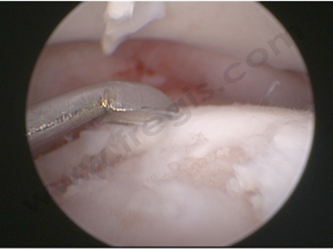

Arthroscopie chez le chien